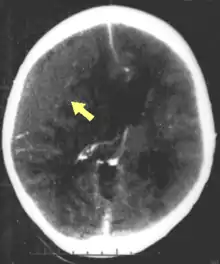

| CT scan showing cerebral contusions, hemorrhage within the hemispheres, and subdural hematoma. There is also displaced skull fracture of left transverse parietal and temporal bones.[2] | |

One type of focal injury, cerebral laceration, occurs when the tissue is cut or torn.[37] Such tearing is common in orbitofrontal cortex in particular, because of bony protrusions on the interior skull ridge above the eyes.[31] In a similar injury, cerebral contusion (bruising of brain tissue), blood is mixed among tissue.[23] In contrast, intracranial hemorrhage involves bleeding that is not mixed with tissue.[37]

Hematomas, also focal lesions, are collections of blood in or around the brain that can result from hemorrhage.[11] Intracerebral hemorrhage, with bleeding in the brain tissue itself, is an intra-axial lesion. Extra-axial lesions include epidural hematoma, subdural hematoma, subarachnoid hemorrhage, and intraventricular hemorrhage.[38] Epidural hematoma involves bleeding into the area between the skull and the dura mater, the outermost of the three membranes surrounding the brain.[11] In subdural hematoma, bleeding occurs between the dura and the arachnoid mater.[23] Subarachnoid hemorrhage involves bleeding into the space between the arachnoid membrane and the pia mater.[23] Intraventricular hemorrhage occurs when there is bleeding in the ventricles.[38]